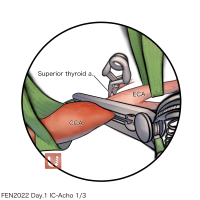

OPExPARK20220405コンテンツシリーズ